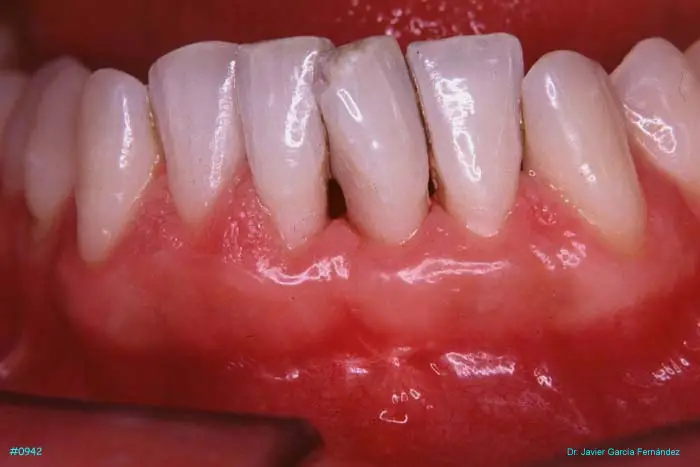

Atlas of Surgical Techniques in Periodontics. Chapter III. Atlas de Técnicas Quirúrgicas en Periodoncia